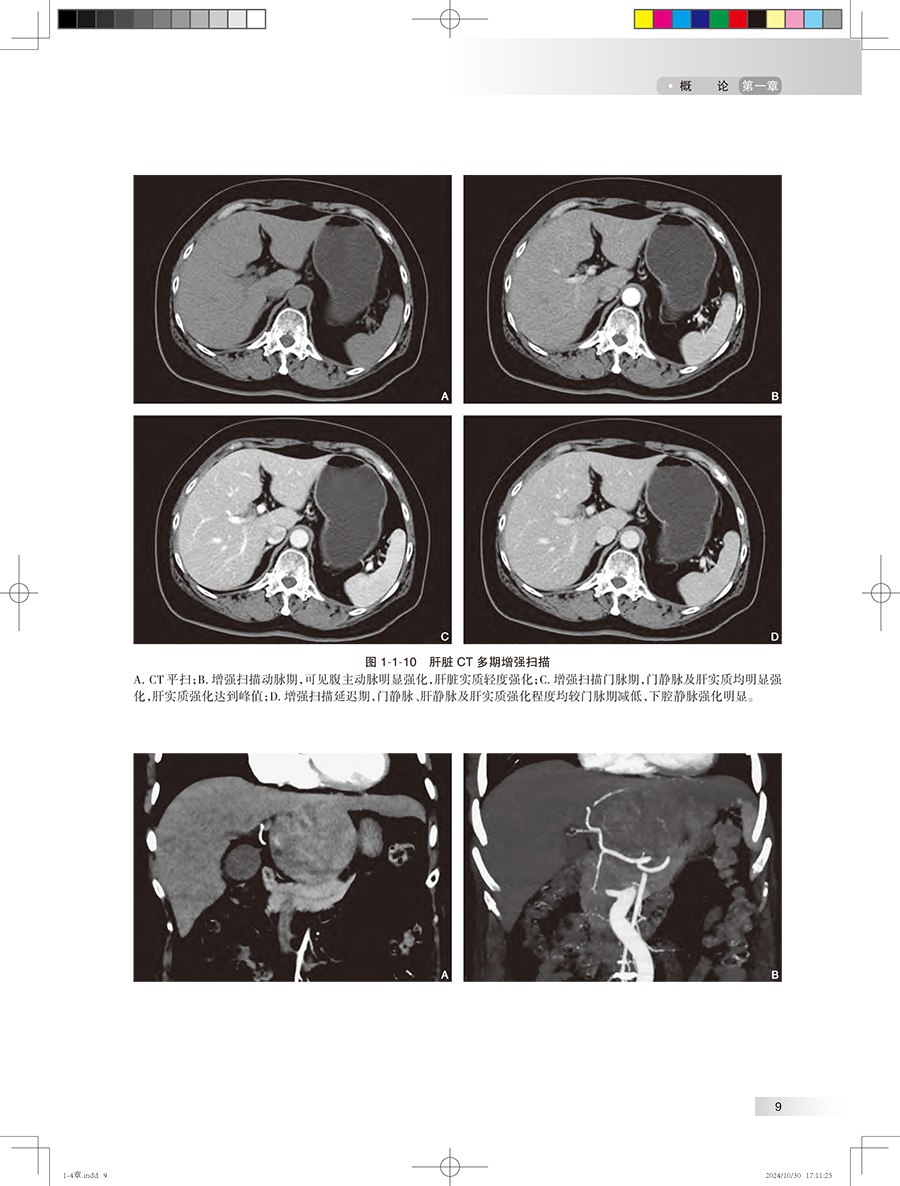

第一章 概 论/1 第一节 肝脏解剖、病理生理、疾病发病情况、影像学的价值 / 1 一、 肝脏解剖/1 二、 肝脏病理生理 / 3 三、 肝脏常见疾病的发病情况 / 3 四、 影像学的价值 / 6 第二节 胆道解剖、病理生理、疾病发病情况、影像学的价值 / 18 一、 胆道解剖/18 二、 胆道病理生理 / 20 三、 胆道系统常见疾病的发病情况/20 四、 影像学的价值 / 23 第三节 胰腺解剖、病理生理、疾病发病情况、影像学的价值 / 26 一、 胰腺解剖/26 二、 胰腺病理生理 / 27 三、 胰腺常见疾病的发病情况 / 27 四、 影像学的价值 / 29 第四节 脾脏解剖、病理生理、疾病发病情况、影像学的价值 / 35 一、 脾脏解剖/35 二、 脾脏病理生理 / 37 三、 脾脏常见疾病的发病情况 / 37 四、 影像学的价值 / 38 第五节 消化道解剖、病理生理、疾病发病情况、影像学的价值 / 42 一、 消化道解剖/42 二、 消化道病理生理 / 44 三、 消化道常见疾病的发病情况/45 四、 影像学的价值 / 46 第二章 临床症状 / 体征/54 第一节 腹痛/54 一、 腹痛的发生机制 / 54 二、 腹痛的分类及病因 / 54 三、 腹痛的临床表现 / 54 四、 腹痛的伴随症状 / 57 五、 影像学检查在腹痛诊断中的应用/57 六、 腹痛的诊断思路 / 58 第二节 腹胀/59 一、 腹胀的发生机制 / 59 二、 腹胀的分类与病因 / 59 三、 腹胀的临床表现 / 59 四、 腹胀的伴随症状 / 60 五、 腹胀的诊治思路 / 60 六、 影像学检查在腹胀诊断中的应用/61 第三节 呕吐/62 一、 定义及概述/62 二、 临床表现及诊断检查 / 63 三、 影像学在呕吐中的应用 / 63 第四节 腹泻/66 一、 定义及概述/66 二、 临床表现与诊断检查 / 66 三、 影像学在腹泻中的应用 / 67 第五节 反酸/70 一、 定义及概述/70 二、 临床表现与诊断检查 / 71 三、 影像学在反酸中的应用 / 72 第六节 嗳气/73 一、 定义及概述/73 二、 临床表现与诊断检查 / 74 三、 影像学在嗳气中的应用 / 74 第七节 吞咽困难/75 一、 定义及概述/75 二、 临床表现与诊断检查 / 76 三、 影像学在吞咽困难中的应用/77 第八节 黄疸/78 一、 定义及概述/78 二、 临床表现与诊断检查 / 78 三、 影像学在黄疸中的应用 / 79 第九节 呕血/81 一、 定义及概述/81 二、 临床表现与诊断检查 / 81 三、 影像学在呕血中的应用 / 83 第十节 便血/83 一、 定义及概述/83 二、 临床表现与诊断检查 / 84 三、 影像学在便血中的应用 / 85 第三章 肝脏影像常见征象 / 86 第一节 肝脏形态改变 / 86 一、 肝脏肿大/86 二、 肝脏缩小/91 三、 肝叶比例失调 / 94 四、 肝裂增宽/96 五、 獭尾肝/99 六、 扇贝征/101 七、 肝包膜回缩征 / 105 第二节 肝脏密度改变 / 110 一、 CT 平扫低密度 / 110 二、 CT 平扫高密度 / 115 三、 地图征/118 四、 龟背征/119 第三节 肝脏信号改变 / 120 一、 T 1WI 高信号 / 120 二、 T 1WI 低信号 / 122 三、 T 2WI 高信号 / 123 四、 T 2WI 低信号 / 125 五、 含脂病灶/127 六、 结中结/129 七、 马赛克征 / 镶嵌征 / 130 八、 门脉周围晕征 / 131 九、 簇状征/132 十、 棒棒糖征/133 十一、 靶征/135 十二、 飘带征 / 水上浮莲征 / 141 十三、 灯泡征/142 十四、 蜘蛛网征/146 十五、 轮辐征/148 十六、 繁星征/149 十七、 环礁征/151 第四节 局灶性病变强化特征 / 153 一、 速升速降/153 二、 速升缓降/156 三、 缓升缓降/160 四、 延迟强化/161 五、 环形强化/167 六、 暂时性肝脏密度 / 信号差异 / 172 七、 周边廓清征/176 八、 血管穿行征/180 九、 翻转征/184 十、 三叶草征/187 十一、 肝胆细胞期低信号 / 191 十二、 肝胆细胞期高信号 / 198 第五节 血管改变/209 一、 门静脉积气/209 二、 轨道征/211 三、 充盈缺损/212 四、 动静脉分流/214 五、 门腔静脉分流 / 217 六、 门静脉海绵样变 / 218 七、 肝静脉早显/221 八、 肝窦阻塞综合征 / 222 第四章 胆道系统影像常见征象 / 231 第一节 胆道病变/231 一、 肝内胆管扩张 / 231 二、 肝外胆管扩张 / 246 三、 肝内外胆管扩张 / 249 四、 胆管狭窄/261 五、 胆管壁增厚/268 六、 胆管肿块/275 七、 胆道积气/279 八、 剪枝征/281 九、 串珠征/282 十、 软藤征/284 十一、 杯口征/286 十二、 双管征/287 十三、 四管征/289 十四、 靶征/291 十五、 云雾征/292 十六、 中心点征/294 十七、 鸟嘴征/296 第二节 胆道病变/299 一、 胆囊肿大/299 二、 胆囊萎缩/300 三、 弥漫性胆囊壁增厚 / 302 四、 局限性胆囊壁增厚 / 305 五、 小帽征/307 六、 珍珠项链征/309 七、 瓷样胆囊/311 八、 隔膜胆囊/312 九、 双胆囊/314 十、 游离胆囊/315 十一、 高位胆囊管 / 316 十二、 低位胆囊管 / 316 十三、 胆囊窝肿块 / 319 第五章 胰腺影像常见征象 / 324 第一节 胰腺形态改变 / 324 一、 胰腺肿大/324 二、 胰腺萎缩/328 三、 胰腺局部凸起 / 332 四、 环状胰腺/336 五、 哑铃形胰腺/337 六、 分叶胰腺/338 七、 胰腺分裂/339 八、 腊肠征/340 九、 胶囊征/341 第二节 胰腺密度改变 / 343 一、 CT 平扫低密度 / 343 二、 CT 平扫高密度 / 349 三、 钙化/353 第三节 胰腺信号改变 / 359 一、 T 1WI 高信号 / 359 二、 T 1WI 低信号 / 365 三、 T 2WI 高信号 / 376 四、 T 2WI 低信号 / 386 第四节 胰管改变/398 一、 胰管扩张/398 二、 胰管狭窄/402 三、 胰管穿行 / 穿透征 / 402 四、 胰管截断征/402 五、 胰管串珠征/404 六、 胰管不相交征 / 405 第五节 肿块/406 一、 富血供肿块/406 二、 乏血供肿块/409 三、 囊性肿块/413 四、 囊实性肿块/419 五、 葡萄征/423 六、 蜂窝征/424 七、 血管穿行征/427 八、 包膜征/430 九、 浮云征/433 第六章 脾脏影像常见征象 / 437 第一节 脾脏形态改变 / 437 一、 脾肿大/437 二、 脾皮质边缘征 / 439 三、 脾楔形不强化区 / 441 第二节 脾脏信号密度特征 / 443 一、 花斑脾/443 二、 脾脏密度增加 / 444 三、 岩石脾/445 四、 脾裂隙征/447 五、 脾包膜钙化/448 六、 T 2WI 灯泡征 / 449 七、 脾气泡征(气 - 液平面) / 452 第七章 食管影像常见征象 / 456 第一节 食管管腔改变 / 456 一、 管腔狭窄/456 二、 管腔扩张/458 三、 鸟嘴征 / 萝卜根征 / 460 四、 三环征/462 五、 腔内异常/463 第二节 管壁改变/465 一、 管壁隆起/465 二、 管壁凹陷/467 三、 管壁增厚/470 四、 管壁僵硬/472 五、 充盈缺损/474 六、 龛影/476 七、 憩室/478 第三节 黏膜改变/480 一、 黏膜破坏/480 二、 黏膜平坦/481 三、 黏膜增宽和迂曲 / 483 四、 环形征/485 第四节 腔外改变/487 一、 食管压迹/487 二、 脂肪间隙异常 / 490 三、 管壁外积气/492 第八章 胃影像常见征象 / 495 第一节 胃腔改变/495 一、 胃腔扩张/495 二、 胃腔缩小/498 三、 葫芦形胃 / 哑铃形胃 / 503 四、 皮革胃/504 五、 胃扭转/506 六、 双泡征/508 第二节 胃壁改变/510 一、 胃壁隆起/510 二、 胃壁凹陷/515 三、 胃壁增厚/518 四、 胃壁僵硬/527 五、 胃壁积气/531 六、 胃壁水肿/532 七、 胃壁肿块/534 八、 龛影/536 九、 充盈缺损/539 十、 憩室/541 第三节 黏膜改变/544 一、 黏膜破坏/544 二、 黏膜平坦/546 三、 黏膜增宽和迂曲 / 547 四、 黏膜纠集/549 第四节 其他改变/550 一、 半月征/550 二、 狭颈征/552 三、 项圈征/554 四、 指压征 / 裂隙征/555 五、 环堤征/557 六、 肩胛征 / 袖口征/560 第九章 肠管影像常见征象 / 565 第一节 肠腔改变/565 一、 肠腔扩张/565 二、 动脉瘤样扩张 / 567 三、 肠腔狭窄/568 四、 肠腔高密度/571 五、 靶环征/572 六、 鹅颈征/574 七、 苹果核征/575 八、 铅管征/577 九、 咖啡豆征/578 十、 鸟嘴征/580 十一、 堆硬币征/581 十二、 哨兵袢征/584 第二节 肠壁改变/587 一、 肠壁增厚/587 二、 肠壁肿块/595 三、 肠壁气体/601 四、 分层强化(三明治征)/604 五、 肠壁憩室/606 六、 肠壁囊性 / 囊实性病变 / 608 七、 肠壁穿孔/611 八、 肠壁溃疡/614 九、 指压痕征(缺血坏死性肠炎)/616 十、 鹅卵石 / 铺路石征 / 617 第三节 肠系膜改变 / 620 一、 梳齿征/620 二、 漩涡征/623 三、 肠系膜混浊征 / 626 四、 缆绳征/629 五、 肠系膜污垢征 / 630 六、 结肠旁高密度环征(肠脂垂)/632 七、 脂肪晕征/634 八、 手风琴征/635 九、 腹茧症/638 十、 脂肪条纹征/641 十一、 脂肪环征/643 中英文名词对照索引/646 登录中华临床影像征象库步骤 / 650